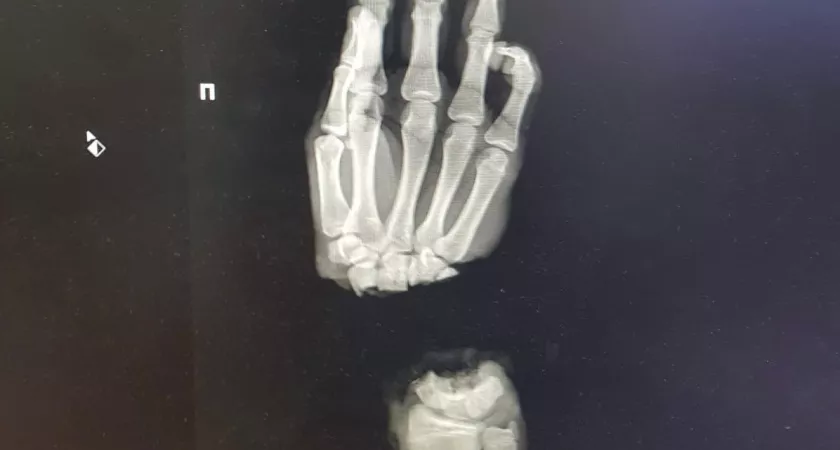

16-летний парень из Владимирской области оказался в нижегородском медучреждении, после того как случайно отрубил себе руку. Молодому человеку вовремя оказали помощь. Об этом сообщают в пресс-службе ПИМУ.

Подростка привезли в университет 1 марта из Коврова. Как выяснилось, он колол дрова и случайно отсек себе кисть. Операцию провели в тот же день вечером. На данный момент молодой человек в стабильном состоянии, кровоснабжение в его руке восстановлено. Однако понадобится еще несколько операций, чтобы он снова мог владеть рукой, насколько это возможно.